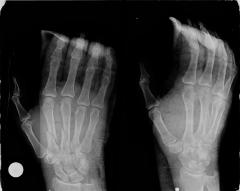

Deformities - Injuries

Fractures of metacarpals and digits of the hand

Fractures of the metacarpals and digits are common in laborers and athletes and can be part of a serious injury that includes tendons, nerves, vessels. The majority are treated surgically with the use of small implants (wires, mini screws and plates). In some cases the implants need to be removed after fracture healing.

These injuries are day-cases. They require a meticulous and strictly followed postoperative program conducted by a properly trained physiotherapist under the surgeon’s supervision.